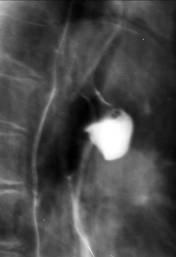

Portiunea terminala a esofagului este īngustata axial cu contururi netede. Esofagul supraiacent este dilatat uneori foarte mult. Umplerea se face de jos īn sus. Exista lichid de staza. Undele peristaltice sunt vii, frecvente dar ineficiente. Staza esofagiana dureaza 3-4 ore. Cardia se destinde la un moment dat producāndu-se evacuarea īntregului continut esofagian (legea totul sau nimic). Aceasta particularitate a evacuarii esofagului diferentiaza cardiospasmul de achalazie.

Cardiospasmul